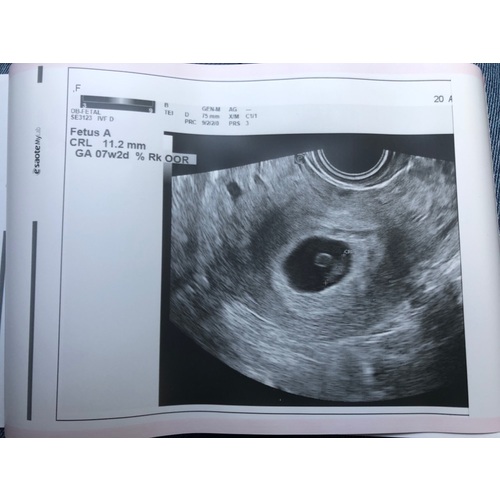

Nu dus opnieuw in verwachting 7+3 en net een goeie echo gehad. Merk wel dat ik het soms lastig vind om blij te zijn. Ik hoop dat dat nog verandert!